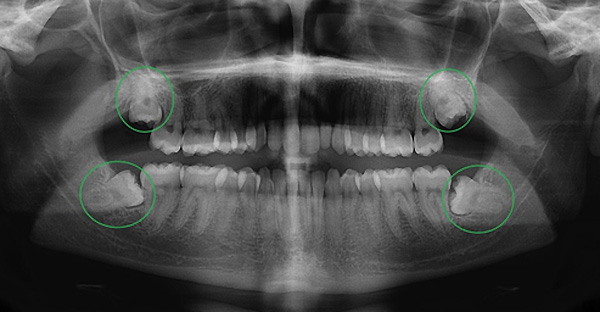

Mọc ngầm: Răng nằm hoàn toàn trong xương hàm và bị nướu che phủ, chỉ có thể phát hiện thông qua phim chụp X quang.

Hệ thống chẩn đoán hình ảnh 3D: Trước khi thực hiện, khách hàng sẽ được chụp phim CT Cone Beam để xác định chính xác vị trí răng, hướng mọc và khoảng cách tới dây thần kinh. Việc lập kế hoạch chi tiết trên không gian 3 chiều giúp bác sĩ kiểm soát hoàn toàn mọi rủi ro trong quá trình nhổ.

Bước 1: Thăm khám và chụp phim CT Cone Beam: Bác sĩ tiến hành kiểm tra tổng quát khoang miệng, chụp phim 3D để phân tích cấu trúc xương và vị trí dây thần kinh quanh răng khôn.